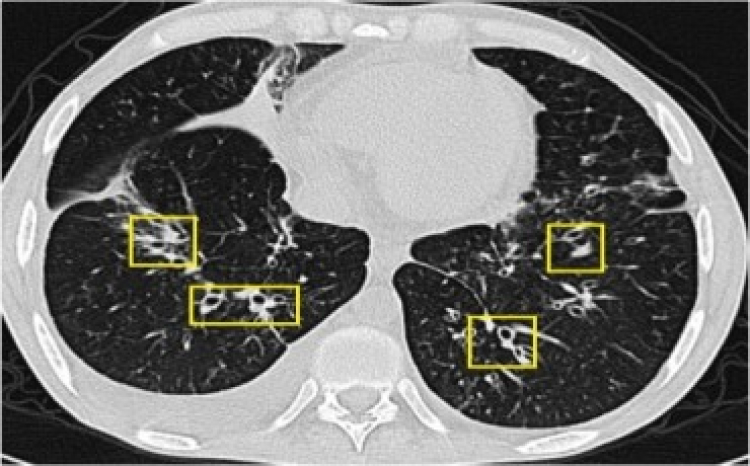

Bronşektazi, akciğerlerde hava taşıyan bronşların iltihaplanması sonucu genişleyerek kronik bir rahatsızlık oluşturuyor.

Sağlık Bakanlığı Koronavirüs Bilim Kurulu Üyesi ve Göğüs Hastalıkları Uzmanı Prof. Dr. Tevfik Özlü, akciğerlere hava taşıyan bronşların iltihap ve enfeksiyon nedeniyle genişlediği kronik bir akciğer rahatsızlığı olan bronşektazi hakkında bilgi verdi. Özlü, "Bronşektazi belirtileri pek çok hastalıkla karıştırılabiliyor. Hastalar uzun yıllar doğru tanı alamıyorlar ve bu da tedaviyi geciktiriyor" dedi.

Bronşektazi hastalarının sıklıkla astım, KOAH veya zatürre gibi farklı hastalıklarla tedavi edildiğini belirten Özlü, "Bu hastalıktaki belirtiler pek çok akciğer hastalığıyla karışabiliyor. Yanlış tanılar ve geciken tedavi, hastaların durumunu daha da kötüleştirebilir. Erken teşhis ve doğru tedavi hayati önem taşıyor" diye konuştu.